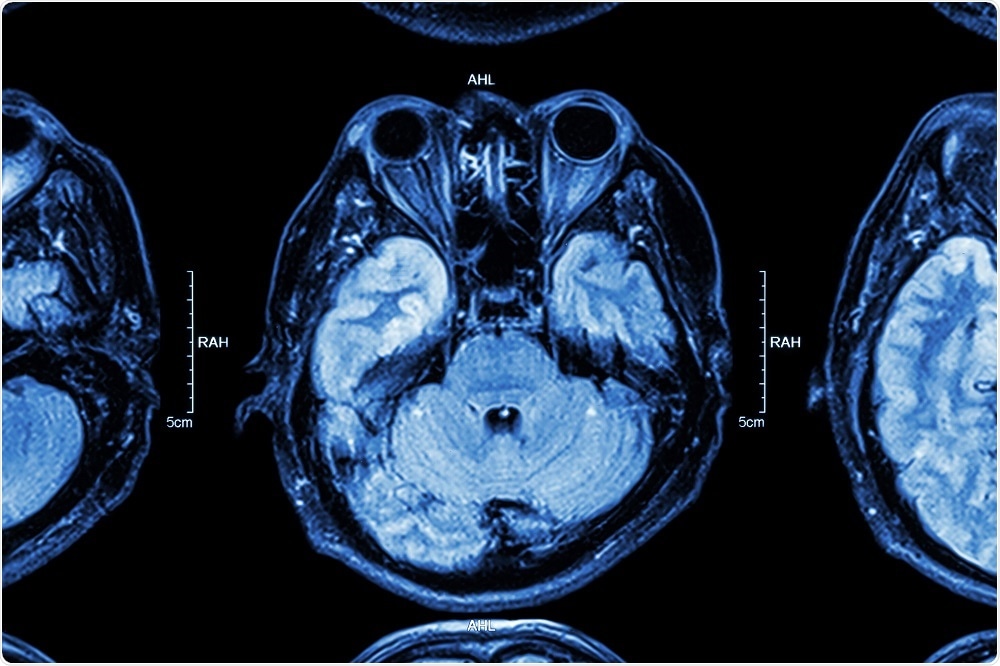

Image Credit: Puwadol Jaturawutthichai / Shutterstock